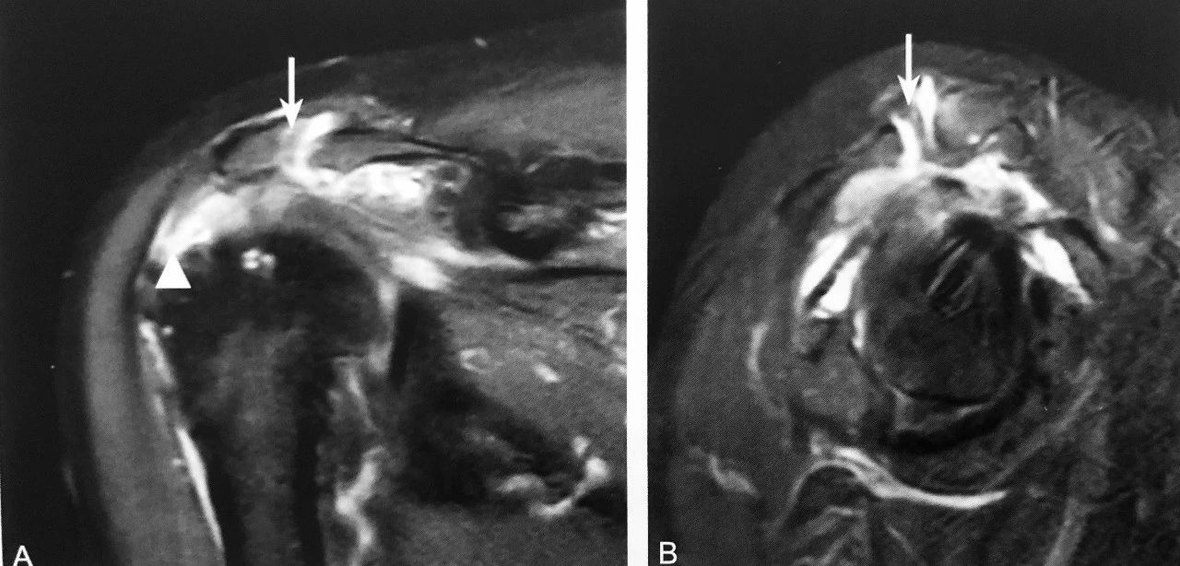

双弧征:A 图正常肘关节侧位 X 线图;B 图患者肘关节 ⅹ 线侧位片示肱骨远端可见两个弧形:一个弧提示肱骨小头游离(细箭头),另一个弧是肱骨滑车游离(粗箭头),双孤征提示肱骨远端冠状面 Dubberley Ⅲ 型骨折;C.同一患者肘关节 Ⅹ 线正位片可见肱骨小头骨皮质不连续(细箭头),肱骨滑车可见线状透亮影(粗箭头);D.CT 的VR 图像可见肱骨远端肱骨小头-滑车骨折

判读要点:

1、肱骨远端冠状面骨折,即肱骨小头-滑车骨折的直接征象;

2、在肘关节侧位片或通过 CT 多平面重建观察;

3、诊断肱骨远端冠状面骨折阳性预测值较高,敏感度相对稍低;4、肱骨小头-滑车骨折应做到手术解剖复位,否则影响预后。